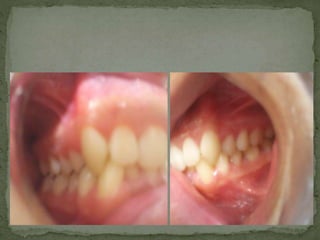

La clase 2 distoclusión se caracteriza por una posición distal de los molares inferiores con respecto a los superiores. Pertenece a la división 2 y tiene como integrantes a Ana Suarez, Bastian Escarate y Camila Toro.